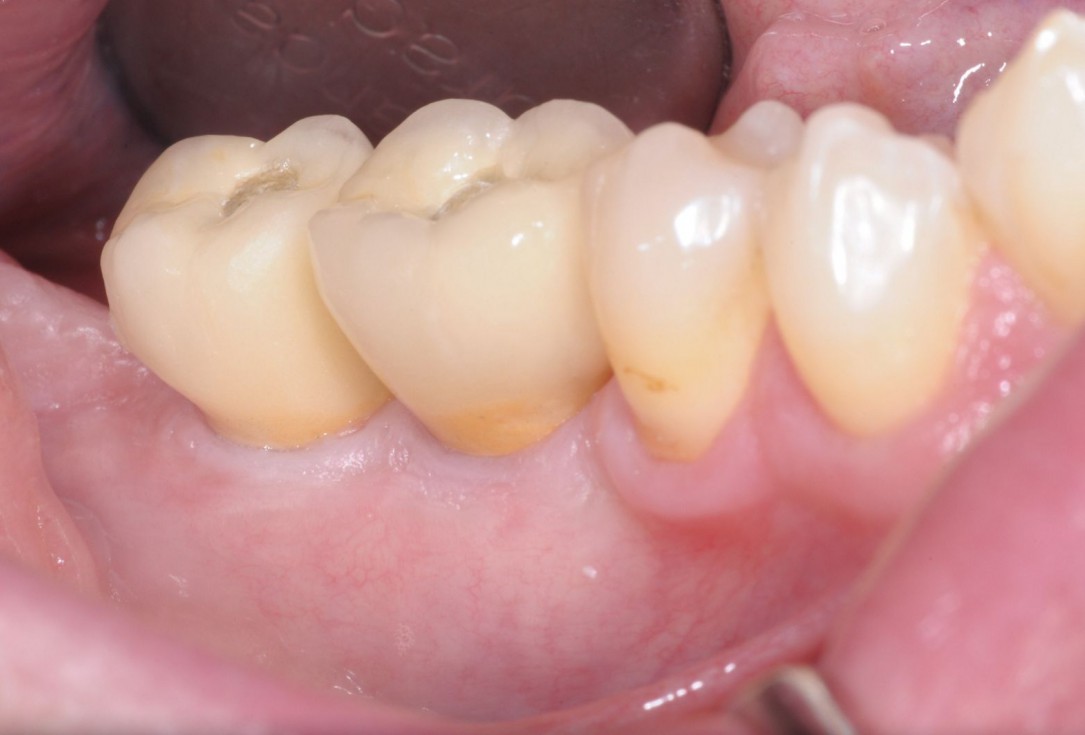

03/28 - Initial clinical situation - massive bone loss in the posterior 4th quadrantThree-dimensional augmentation with maxgraft® cortico - Dr. R. Würdinger

Initial clinical situation: Free end situation in quadrant three and four